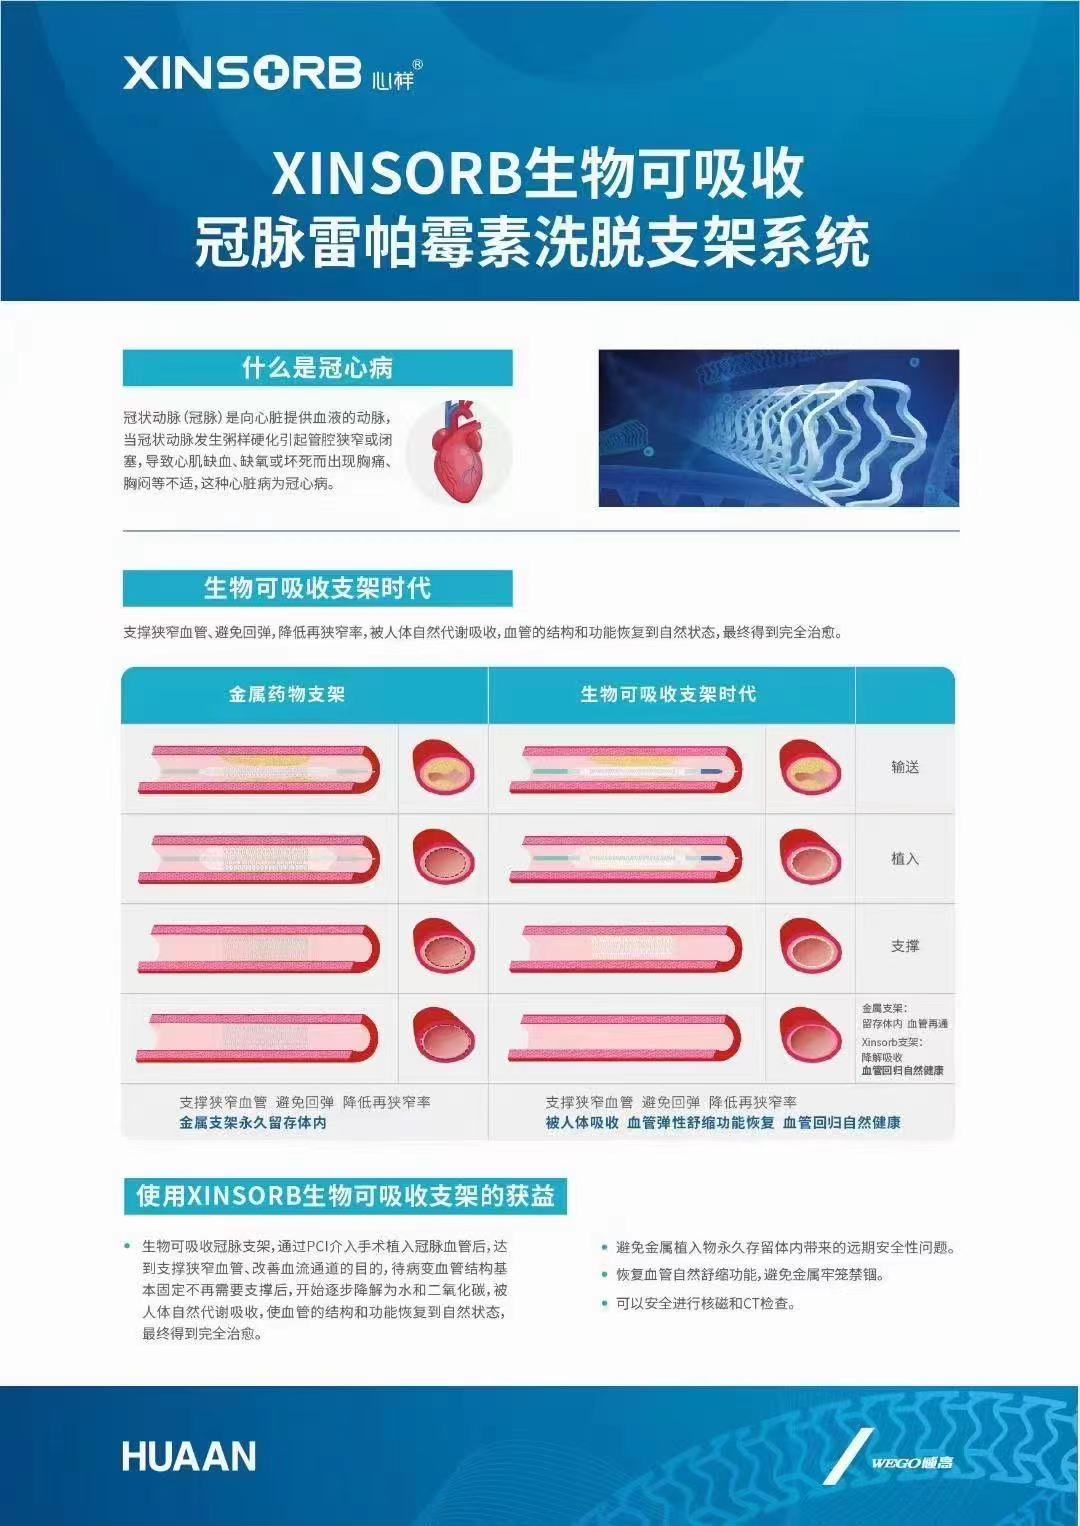

祝賀 牡丹江心血管病醫院關春普 主任團隊成功為患者植入Xinsorb生物可吸收支架!

祝賀 牡丹江心血管病醫院關春普 主任團隊成功為患者植入Xinsorb生物可吸收支架!